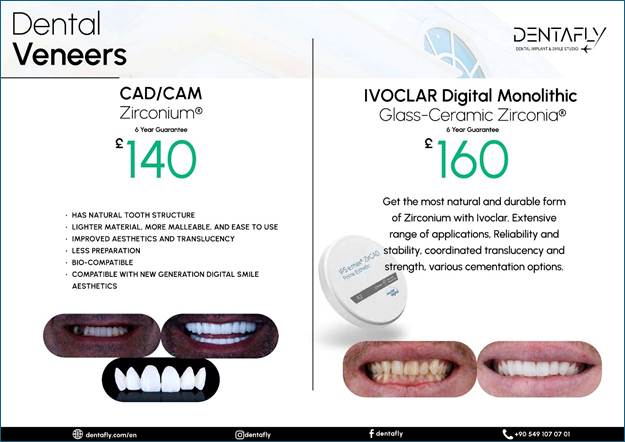

To AI Edge Ok I went to turkey to Antalya

to a company called Dentafly but before I left I sent picture through what’s

app of my teeth and received a quote of 1325 pounds the invoice stated I will

receive STRAUMMAN NEODENT IMPLANTS N ABUTMENTS

2 IMPLANTs but when I got there I see their head dentist and he

advise me to get better ones named Hiossen NH Hydrophilic Implants and one

extra crown which we never realized I needed. He quoted 375 for the extras.

The price of the crows is £125 pounds as in the invoice above, so he charged

an extra £250 pounds for the implant upgrades as I was told. I have got home now and

checked the first invoiced and it has a section with pictures and texted

titled as Dental Implants Which brands we are working with and

states Hiossen NH Hydrophilic Implants 490 pounds and Straumann BLX Implants

750 pounds. so, he charged me more and

give me rubbish ones by the pricing in their invoice. The image below is from the

invoice and proves the original Implant make!

The image provided below is

also from the first invoice and serves as evidence of the pricing listed in

their advertisements. It is important to note that there are six distinct

brands featured, accompanied by only three images. This potentially leads to

confusion, as each brand has its own unique pricing structure. Upon reviewing

their website, it becomes clear that these brands should each have their own

corresponding images; however, this is not the case. Furthermore, the layout is

compounded by the presence of only two divider lines, which implies that each

section contains multiple advertisements rather than a single advertisement

per brand. This setup undermines the clarity of the pricing information, as

it suggests a mix of prices for two different products within the same

section.

Evidence that these brands

should each have their own corresponding images, as they are their own brands,

is as below! https://dentafly.com/treatments/antalya-implant-treatment/